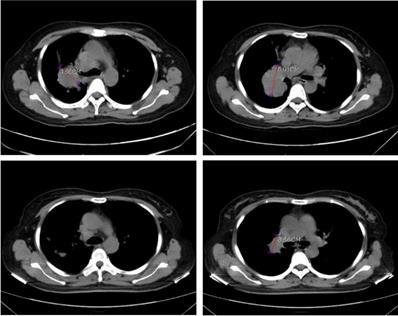

In order to validate the feasibility of leveargeing ctDNA-based testing to guide targeted therapy in SCLC, a 49-year-old female with a confirmed diagnosis of extensive-stage SCLC was subjected to NGS analysis of her peripheral blood using the 150-gene panel described above. The patient presented with a right upper lobe lesion measuring 4.66 cm, a right hilar lesion measuring 5.91 cm and multiple hepatic and bone metastases and had failed two cycles of chemotherapy with etoposide plus cisplatin previously. NGS anlaysis revealed mutations in EGFR (L858R at 56.4% and T790M at 55.14%), ATM (R3008H at 0.52%), PTEN (R130Q at 56.82% and S59* at 8.92%; * denotes a stop codon), and TP53 (P278S at 68.89%). Considering the co-occurrence of L858R and T790M, the patient was started on osimertinib (80 mg/day, po) on June 1st, 2020. A computerized tomography (CT) scan conducted on June 26th, 2020 showed that the patient had achieved partial response (PR) with almost complete regression in the right upper lobe lesion and a 38.1% reduction in the right hilar lesion (Figure 3). Blood tests performed on July 2nd, 2020 also showed a remarkable drop in the levels of tumor biomarkers since the onset of osimertinib treatment (Table 3). The patient continued to receive osimertinib until disease progression (PD) as shown by a CT scan on September 22nd, 2020.

Figure 3

Computerized tomography (CT) scans showing tumor regression in the right upper lobe lesion and the right hilar lesion following treatment with osimeritinib in an extensive-stage SCLC patient harboring EGFR L858R and T790M mutations.